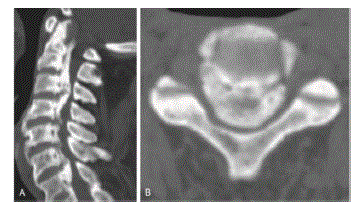

Que achado radiográfico pode ser identificado na tomografia abaixo (Figura 2)?

Caso 4. Paciente de 62 anos, sem comorbidades, após sofrer queda em casa ao escorregar em chão molhado, evoluiu com perda de força nas mãos; conseguia mover as pernas, mas já não conseguia deambular sozinho, apenas com auxílio e em terrenos planos. Apresentava também parestesias leves e discreto distúrbio esfincteriano.

Em relação ao caso 4, assinale a alternativa CORRETA.